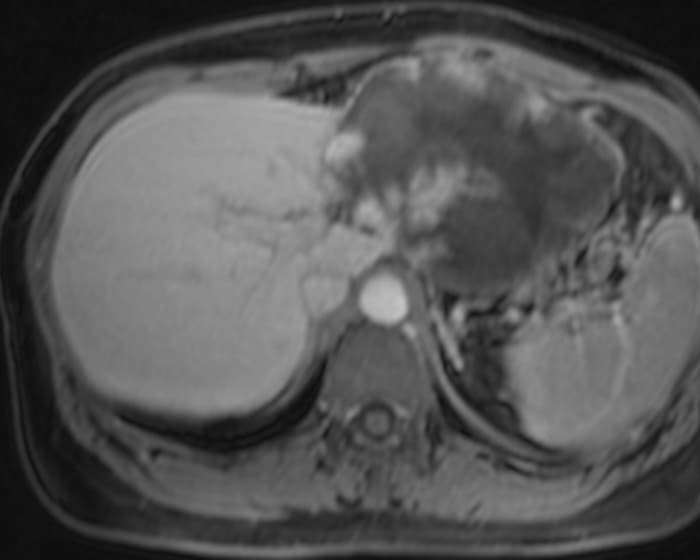

U máu gan

» Thông tin: Nữ giới – 47 tuổi.

» Lâm sàng: Đau thượng vị.